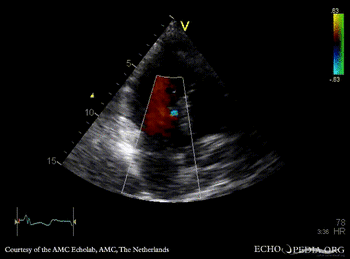

E00502.gif E00503.gif

PLAX: concentric hypertrophy of left ventricle, SAM of AMVL PLAX with Color Doppler: high velocity turbulent flow in LVOT